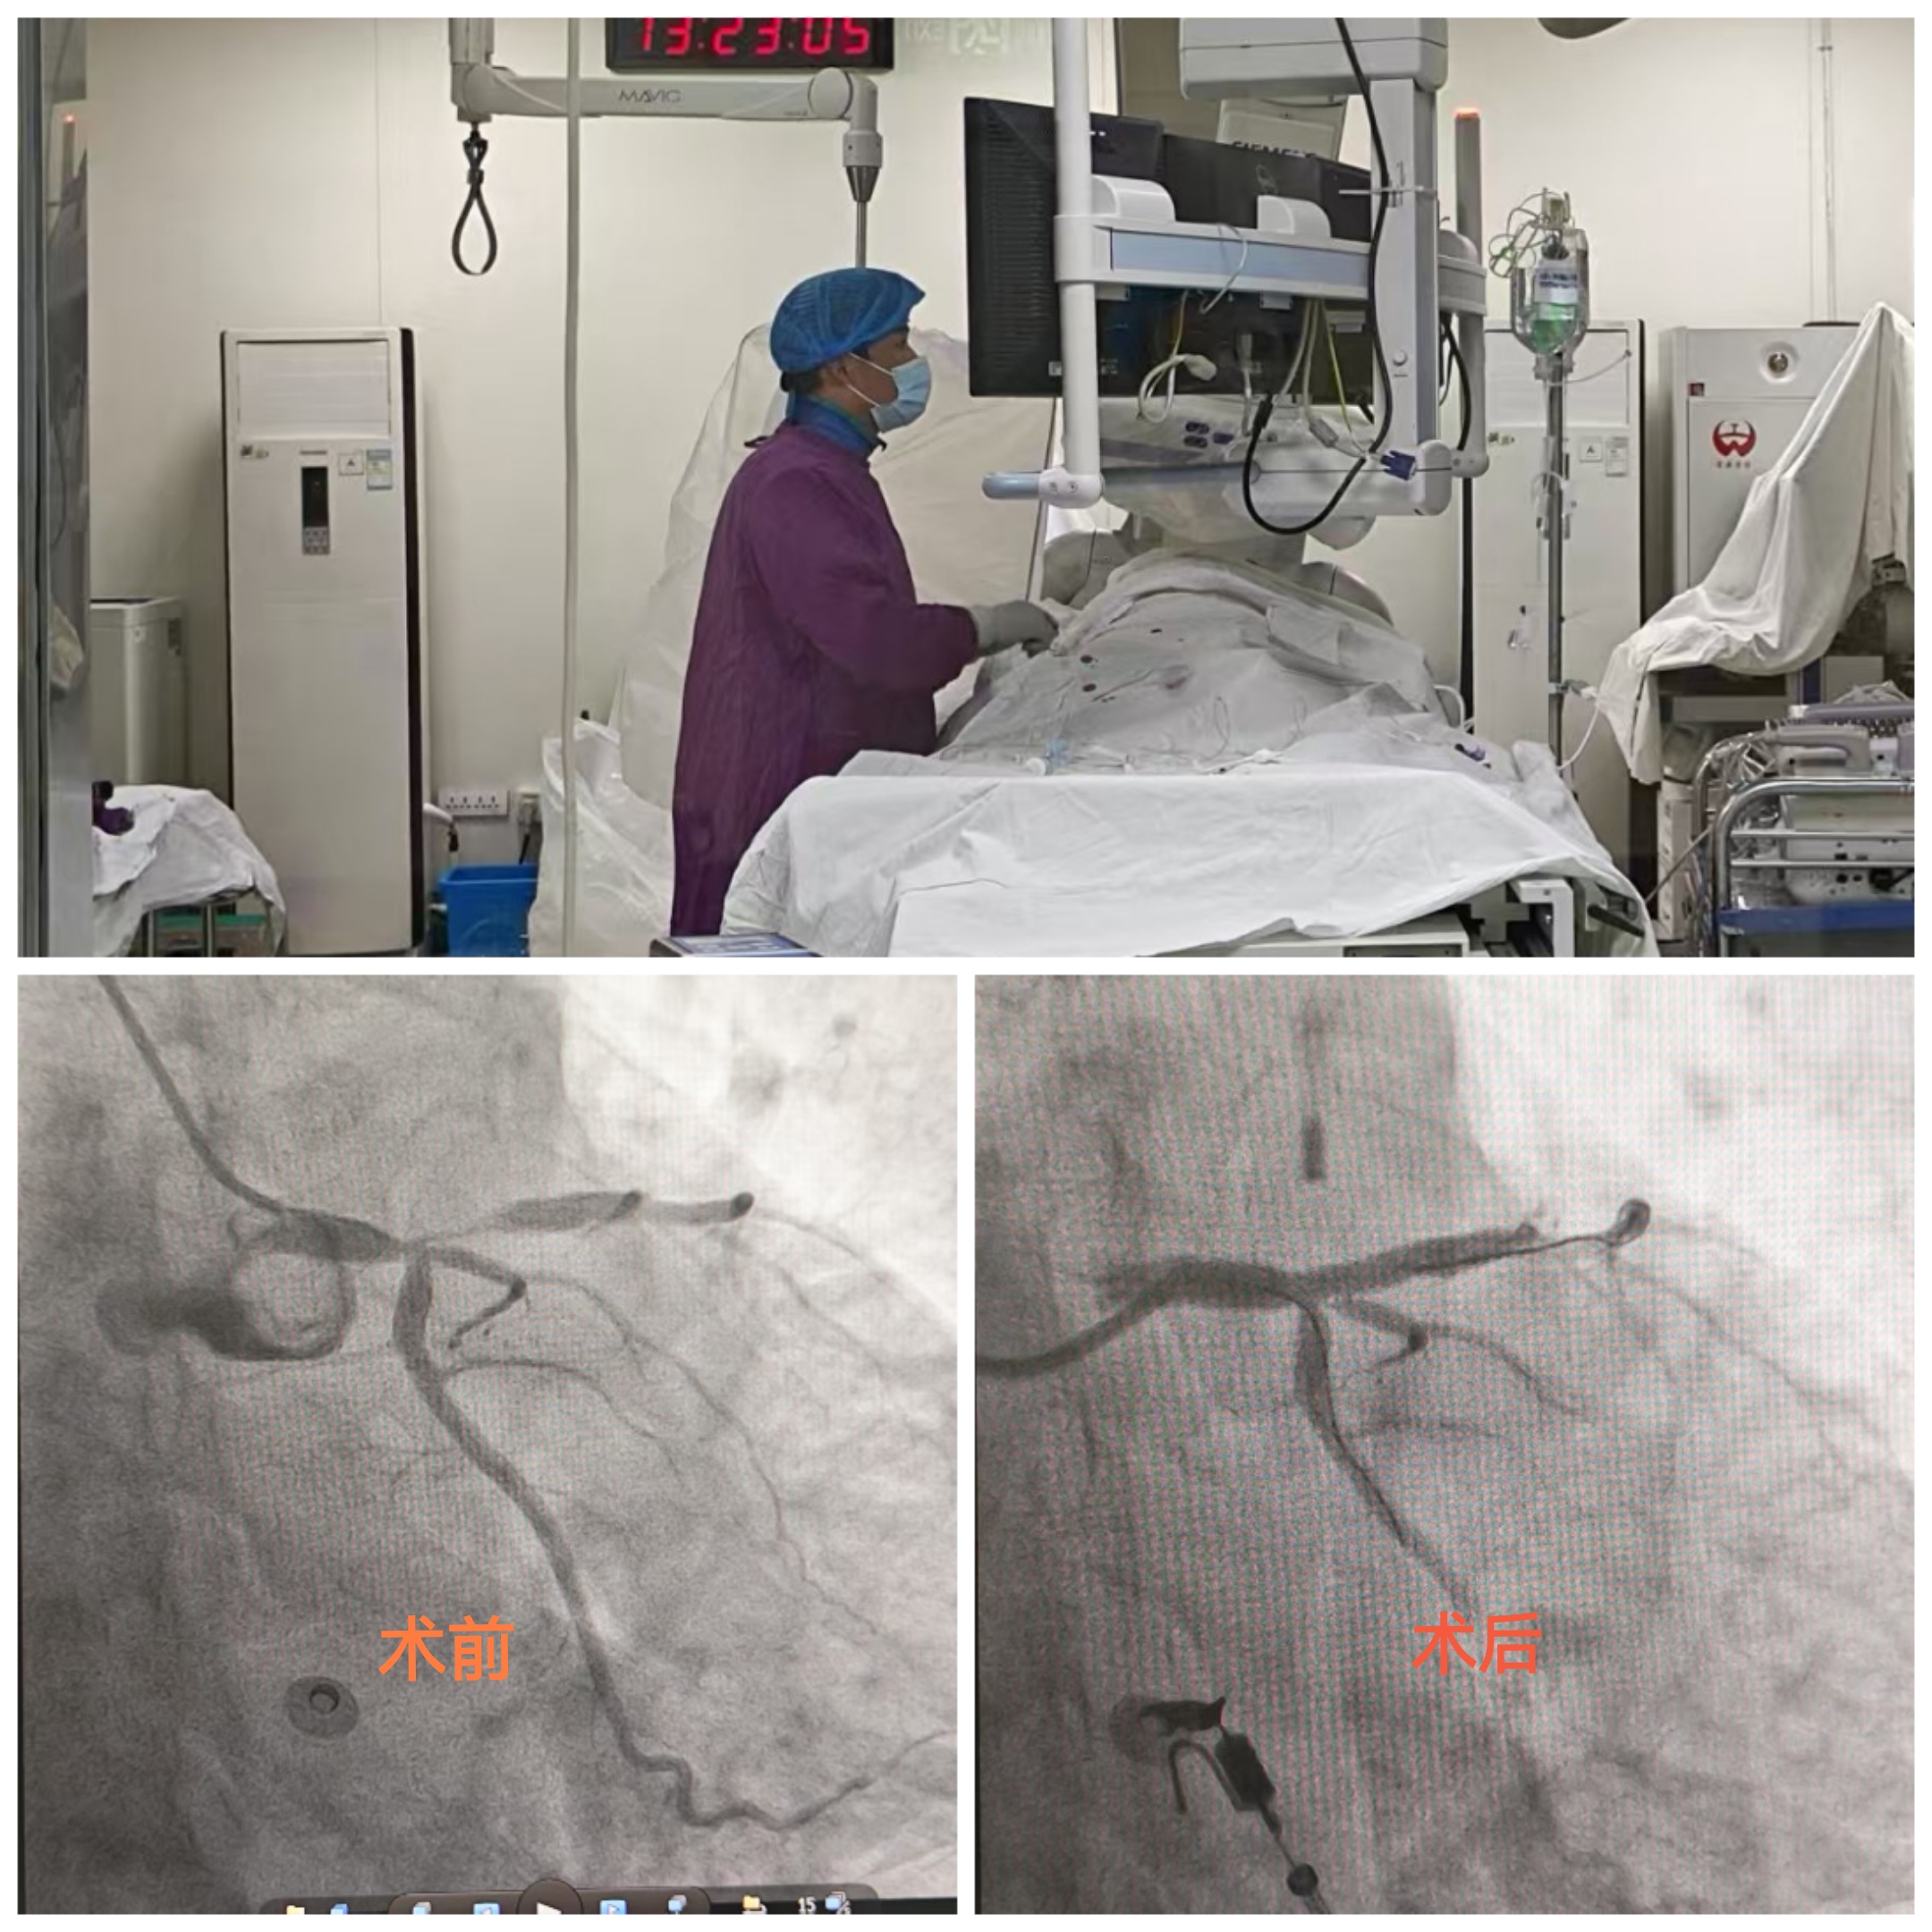

一位老人在健康管理中心进行健康体检,行心电图检查时提示V1-V5异常Q波伴ST段抬高,T波改变。经验丰富的心功能科医生敏锐捕捉到异常波形,凭借专业的医学判断,高度怀疑患者为急性心肌梗死。心功能科医生立即按危急值流程通知健康管理中心医护人员。健康管理中心迅速开通绿色通道,安排患者立即前往胸痛门诊就诊。胸痛门诊医护团队第一时间启动胸痛中心患者救治流程,完善相关检查。经确诊,患者高度怀疑为急性心肌梗死,情况十分危急。心血管内科一病区医生立即启动程序为患者进行救治,成功为其植入心脏支架,开通堵塞血管,患者转危为安。此次救治过程,从体检时发现异常到手术成功,各环节无缝衔接、高效运转,充分展现了医院在急危重症救治方面的卓越能力。

文图:健康管理中心